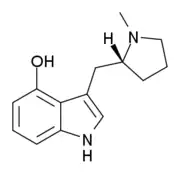

| 4-HO-pyr-T | artificial | 4-OH | (CH2)4 | 3-[2-(Pyrrolidin-1-yl)ethyl]-1H-indol-4-ol | 63097-26-7 | |

Lucigenol | (R)-3-(N-methylpyrrolidin-2-ylmethyl)-4-hydoxyindole | 250672-65-2 |